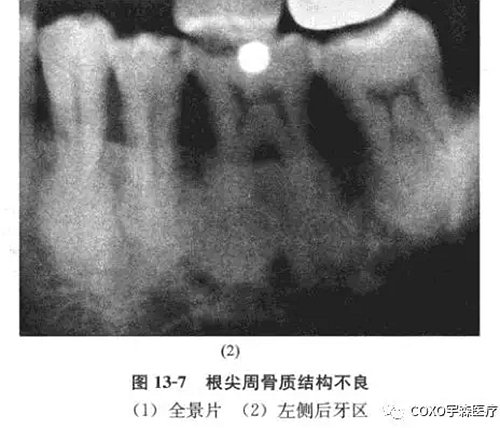

x線片示:雙側(cè)后牙區(qū)高密度陰影(圖13-7),初步診斷:雙側(cè)后牙區(qū)根尖周骨質(zhì)結(jié)構(gòu)異常,伴感染,收入院。

晚期(成熟的根尖周牙骨質(zhì)結(jié)構(gòu)不良)病變在活髓牙根端,孤立或多發(fā)性,x線片密度高,影像均勻一致,大多數(shù)為圓形或卵圓形,但偶爾為不規(guī)則形,組織學(xué)上幾乎完全由不同比例的致密牙骨質(zhì)和骨組織形成,腔隙或血管間隙很少。

筆者所報(bào)道之病例,根尖周牙骨質(zhì)結(jié)構(gòu)不良的表現(xiàn)各階段都有,但以成熟階段為主,牙根已變成圓形或橢圓形,有時(shí),病變擴(kuò)大,致密質(zhì)骨膨脹,粘膜潰爛,繼發(fā)感染,也可逆行性引起牙髓炎癥、甚至壞死,該患者就出現(xiàn)過因牙痛就診行根管治療術(shù)的經(jīng)歷。